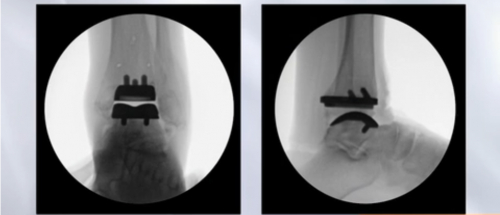

(全踝关节Infinity假体植入效果)

(Inbone II 植入效果图)